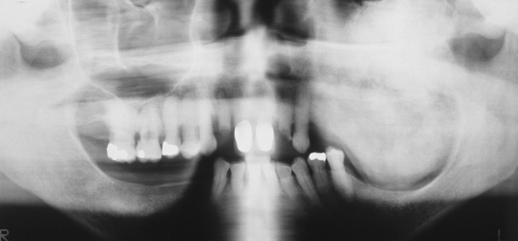

osteoblastoma

notice it is >2cm

osteoma